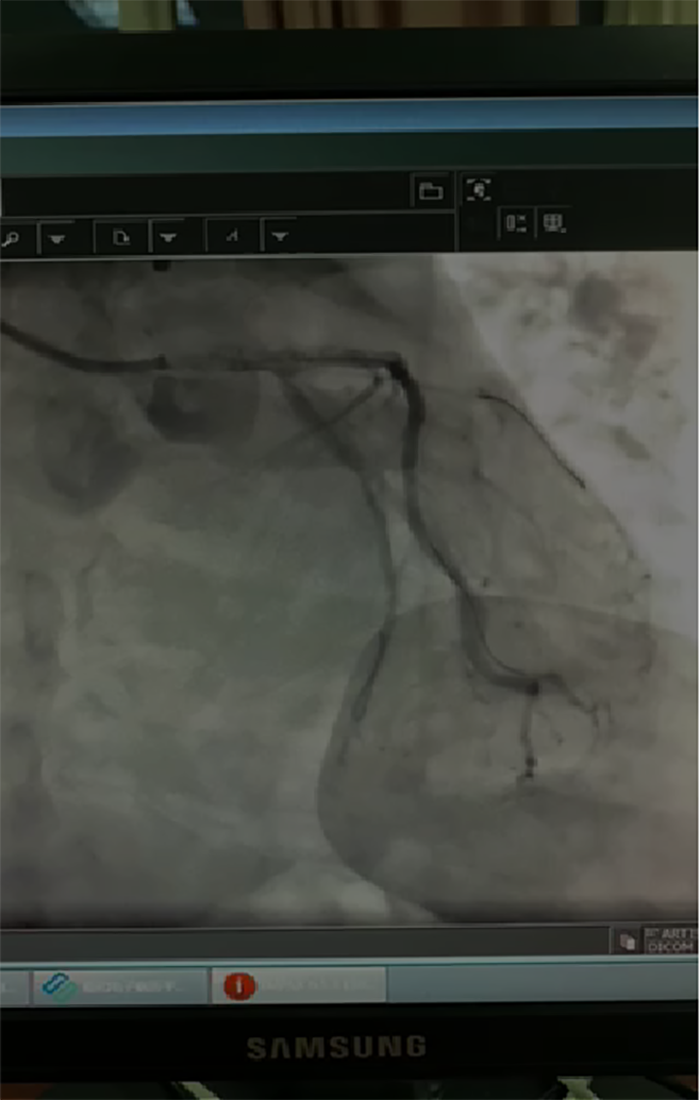

“在冠状动脉造影术下,显示患者心脏左主干加上三支血管病变,这种情况基本属于九死一生。”跳蛋视频 心血管内科主任蔡亚滨介绍,多学科联合抢救团队马上确定救治方案,ICU团队先上V-A ECMO(体外膜肺氧合技术,起到一个人工心肺的作用)稳定患者状况,随后心血管内科介入团队在ECMO保护下进行介入手术(PCI),在患者左主干前降支、回旋支、右冠植入支架,90分钟后顺利完成手术。术后第4天,患者心率、血压稳定,顺利拔除ECMO动静脉导管,术后第10天转入普通病房继续诊治。